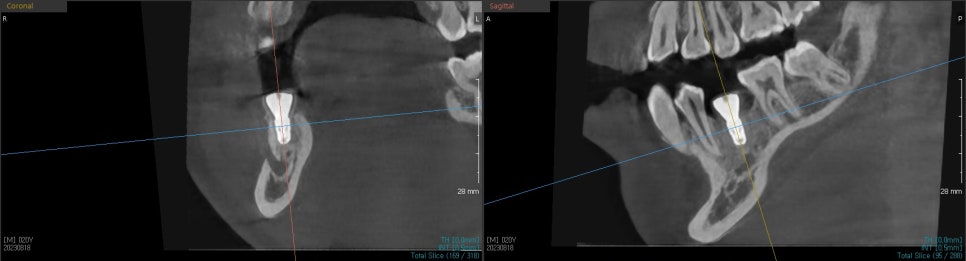

임플란트를 심을 위치를 확인하고 신경까지의 거리를 보기 위해

엑스레이를 찍어 확인합니다.

CT를 찍어 임플란트가 잘 심어졌는지

확인 후 수술을 마무리 하였습니다.